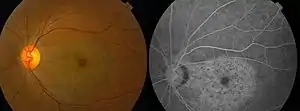

| Chloroquine retinopathy[2] | |

With continued drug exposure, there is progressive development of a bilateral atrophic bull's-eye maculopathy and paracentral scotomata, which may in severe cases ultimately spread over the entire fundus, causing widespread retinal atrophy and visual loss.